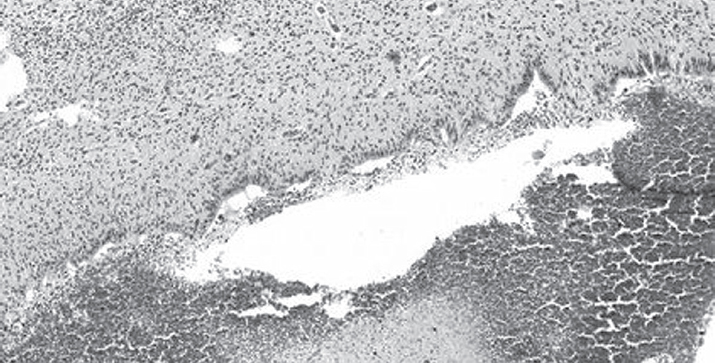

На микрофотографии видны сосуды микроциркуляторного русла, имеющие разный размер и форму, располагающиеся небольшими группами и по отдельности. Просвет большей части сосудов расширен и заполнен форменными элементами крови с преобладанием эритроцитов. Кроме этого, визуализируются единичные, извилистой формы, спавшиеся неполнокровные кровеносные сосуды. Выстилка сосудов микроциркуляторного русла представлена эндотелием, располагающимся преимущественно в один ряд; местами, в части изгиба сосуда, отмечается наложение друг на друга эндотелиальных клеток. Большая часть эндотелиоцитов овальные, другие чуть вытянутой формы, располагающиеся в отношении друг друга не плотно, межклеточные контакты широкие. В отдельных кровеносных сосудах отмечается слущивание эндотелия с дефектом сосудистой стенки и выходом форменных элементов крови во внесосудистое пространство. Кисты, определяющиеся преимущественно на границе герминативного матрикса с белым веществом головного мозга, формировались скорее всего в результате деструктивного отека и характеризовались образованием полостей вокруг сосуда. В отдельных участках вещества головного мозга перивентрикулярной области определяются диффузные кровоизлияния с очагами геморрагических некрозов и пропитыванием кровью ткани субэпендимального пространства (рис. 2).

Рис. 2. Диффузные кровоизлияния с очагами геморрагических некрозов и пропитыванием кровью ткани субэпендимального пространства. Окраска гематоксилином и эозином. Ув. ×10 / Fig. 2. A diffuse hemorrhages with foci of hemorrhagic necrosis of the subependymal area (H&E stain). Magnification ×10